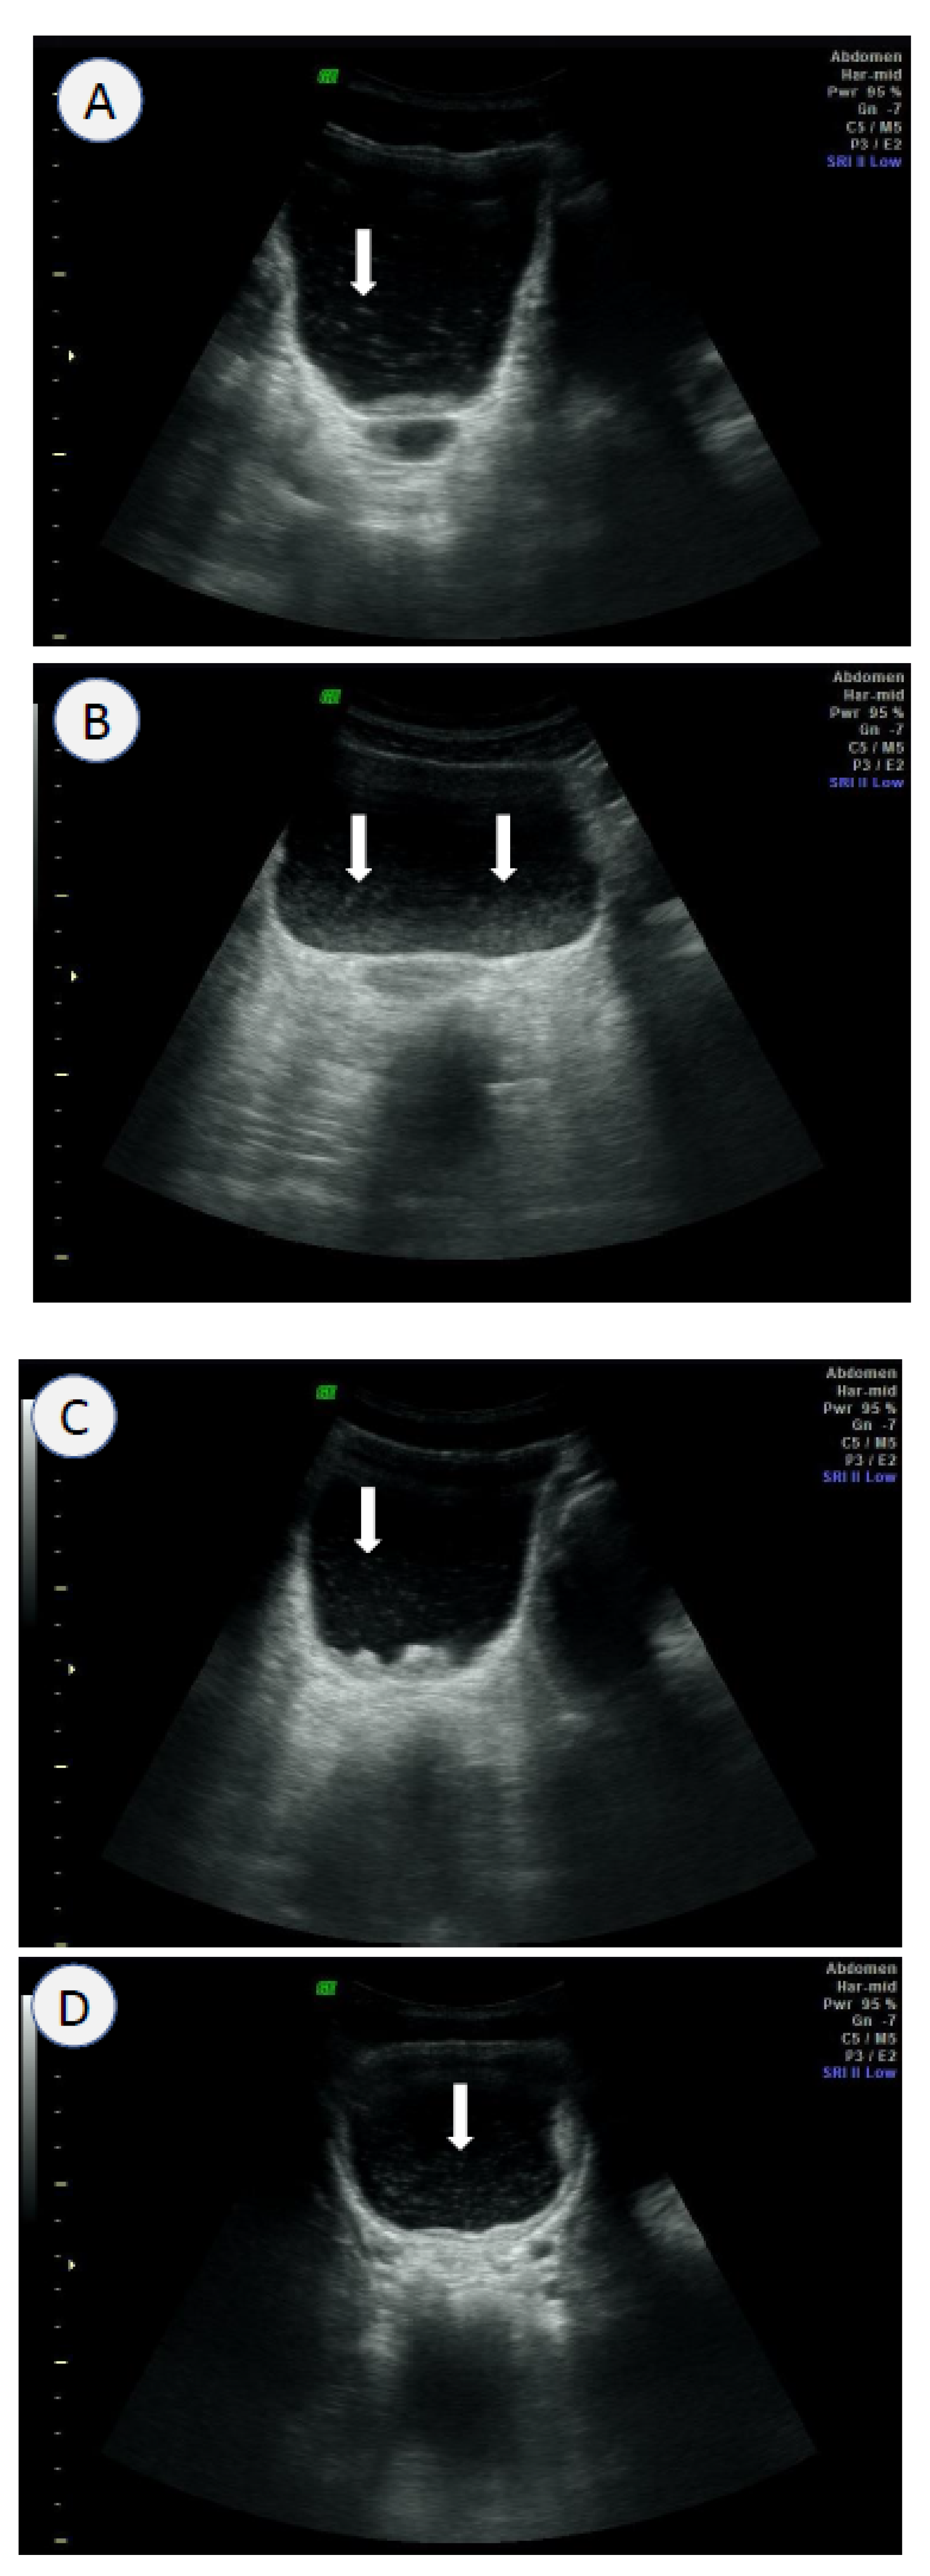

3.4. Ultrasound Scanning

- Kim, M.J.; Hong, S.-T.; Jin, Y.; Ryu, K.; Kim, S.H.; Saeed, A.A.W.; Jeoung, H.G.; Lee, Y.H. Significance of echogenic snow sign as an ultrasonography finding for diagnosis of urogenital schistosomiasis. Am. J. Trop. Med. Hyg. 2016, 95, 842–848. [Google Scholar] [CrossRef]

- Cozzi, D.; Bertelli, E.; Savi, E.; Verna, S.; Zammarchi, L.; Tilli, M.; Rinaldi, F.; Pradella, S.; Agostini, S.; Miele, V. Ultrasound findings in urogenital schistosomiasis: A pictorial essay. J. Ultrasound 2019, 23, 195–205. [Google Scholar] [CrossRef]

| Ultrasound | High sensitivity (>80%) High specificity (>80%) Morbidity information of UGS on site Detection of other co-morbidities | Experienced sonographer Expensive sonograph Feasible for small-scale surveys | Poor Expensive method Feasible with a portable sonograph |